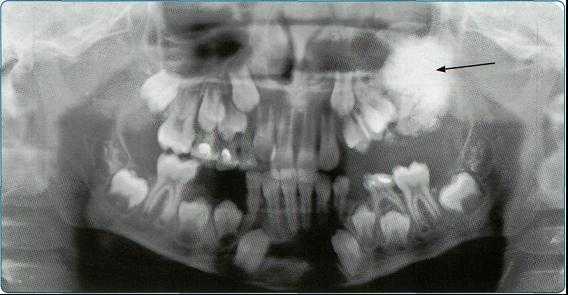

На основании панорамных снимков диагностируют кариес и его осложнения, кисты разных типов, новообразования, повреждения челюстных костей и зубов, воспалительные и системные поражения. У детей хорошо определяется состояние и положение зачатков зубов.

Ортопантомограммы демонстрируют взаимоотношения зубов верхнего ряда с дном верхнечелюстных пазух и позволяют выявить в нижних отделах пазух патологические изменения одонтогенного генеза.

Особенно важно использовать ортопантомографию в детской стоматологии, где она не имеет конкурентов в связи с низкими дозами облучения и большим объемом получаемой информации. В детской практике ортопантомография помогает диагностировать переломы, опухоли, остеомиелит, кариес, периодонтиты, кисты, определять особенности прорезывания зубов и положение зачатков.